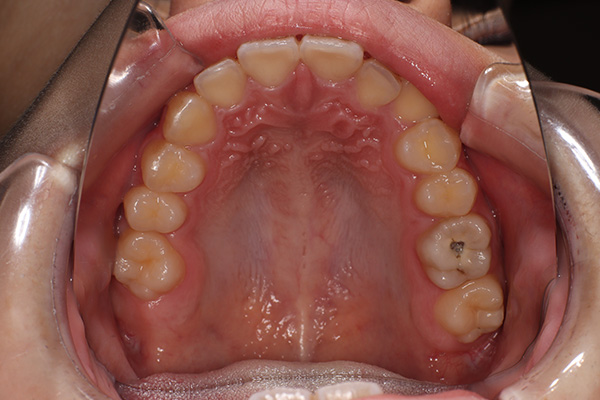

「歯に穴が空いて食事の時に痛む」という主訴でご来院されました。他院で治療を受けた箇所であり虫歯が非常に深く、通常であれば神経を全て抜く「抜髄(ばつずい)」が必要な状態でした。今回は若年者ということもあり将来的なことを鑑み神経の一部を温存する「部分的断髄法(VPT)」を提案しました。高い殺菌性と封鎖性、そして組織の再生を促す効果を持つMTAセメントを使用して神経を保護し、歯質削除量を最小限とするためコンポジットレジン修復とし、最終的には強度と審美性に優れたセラミックで再修復する計画を立案しました。

| 患者 | 10代男性 |